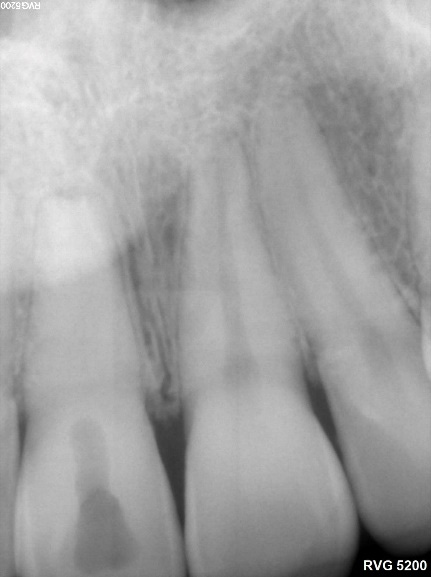

Tooth #11 with a calcified canal following traumatic injury

Tooth #11 with a calcified canal following traumatic injury. The tooth was symptomatic with positive percussion. The referring dentist attempted root canal treatment without success. The patient presented with a CBCT scan.

Post-operative radiograph

Intraoperative radiograph

Mater cone radiograph